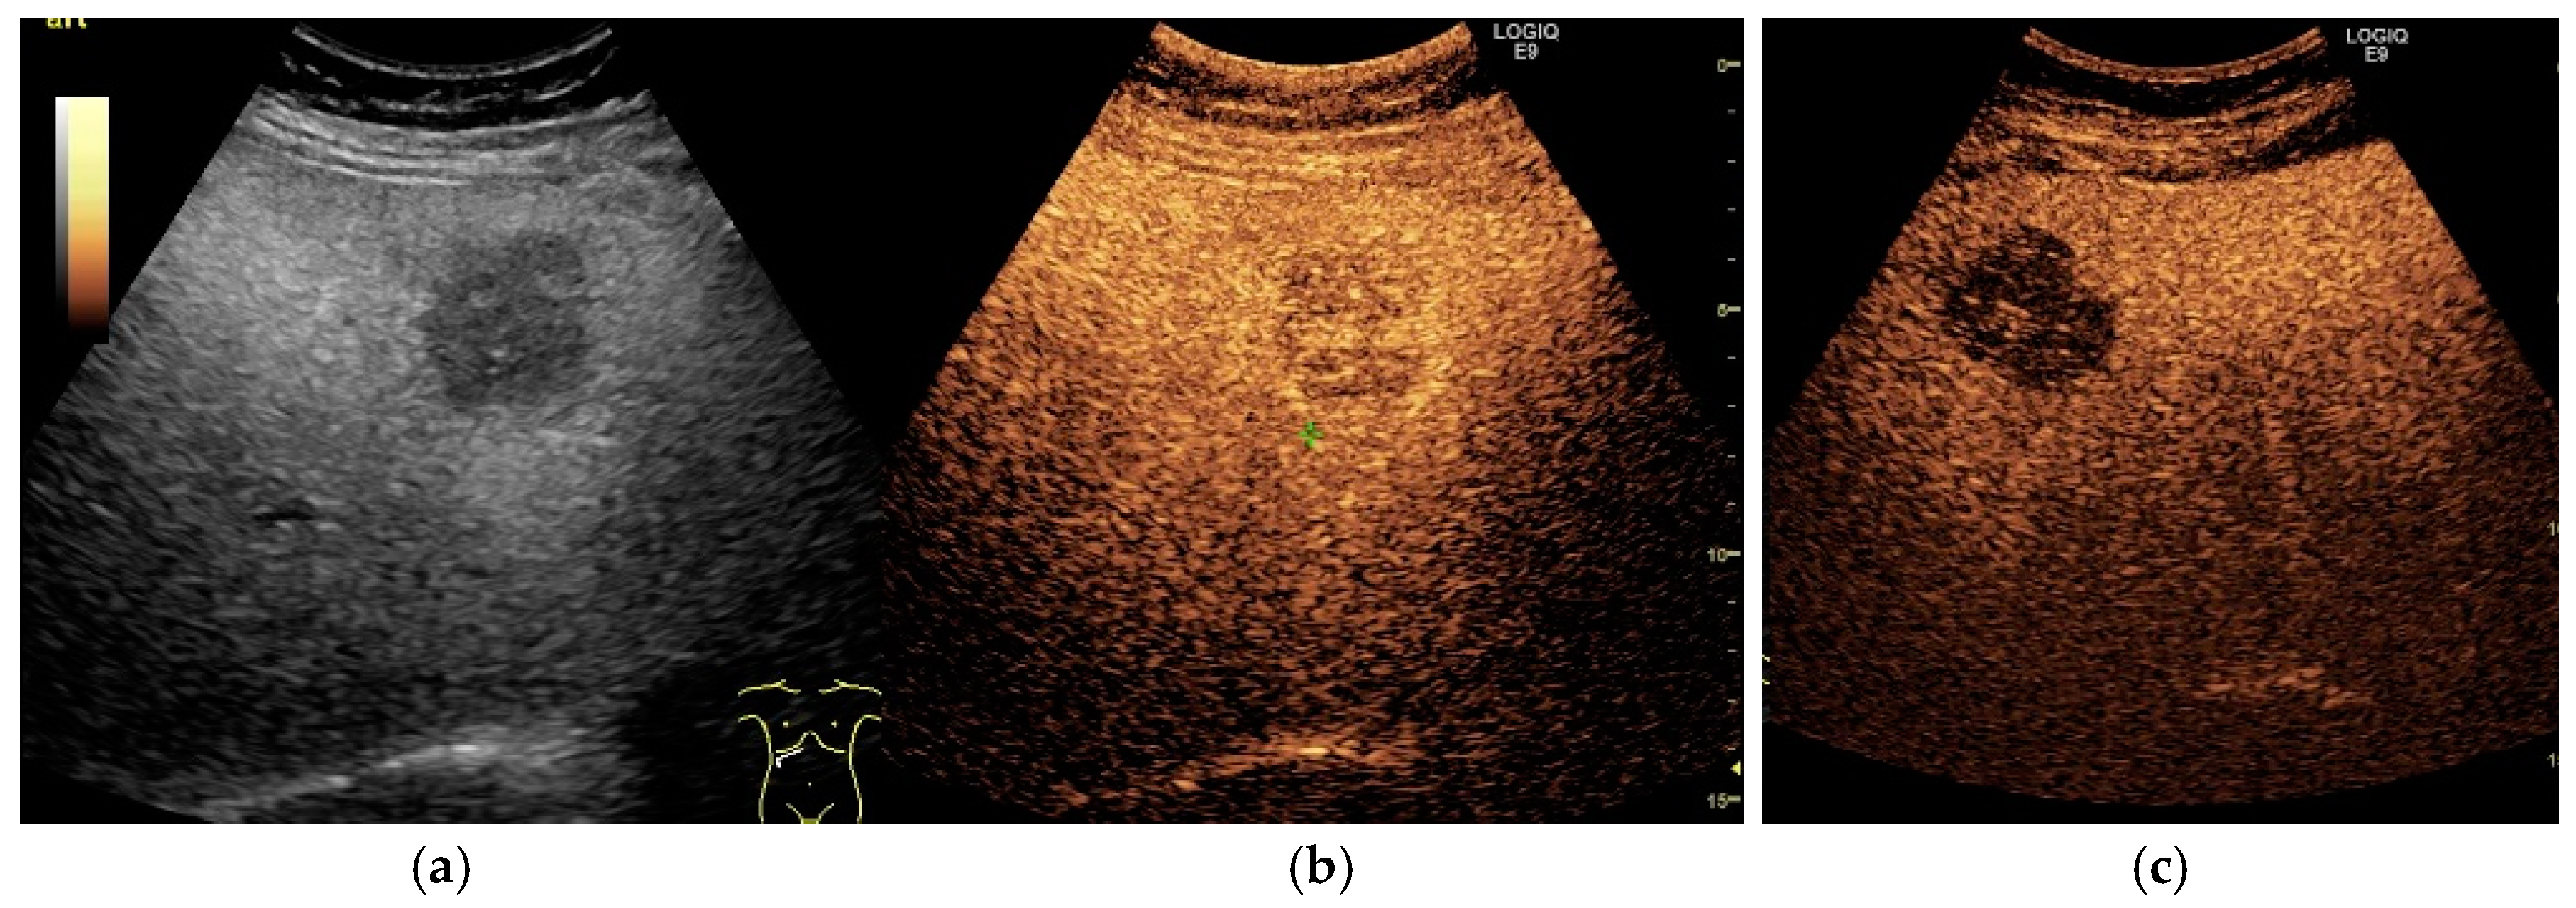

3. Contrast-Enhanced Ultrasonography (CEUS): An Add-on to the Diagnostic Power of Ultrasonography in NAFLD-Related HCC

3.3. The Evaluation of FLLs, Including HCC, in NAFLD Patients Using CEUS

3.3.1. Diagnostic Features of Hepatocellular Carcinoma on CEUS

3.3.2. HCC Particularities in NAFLD Patients